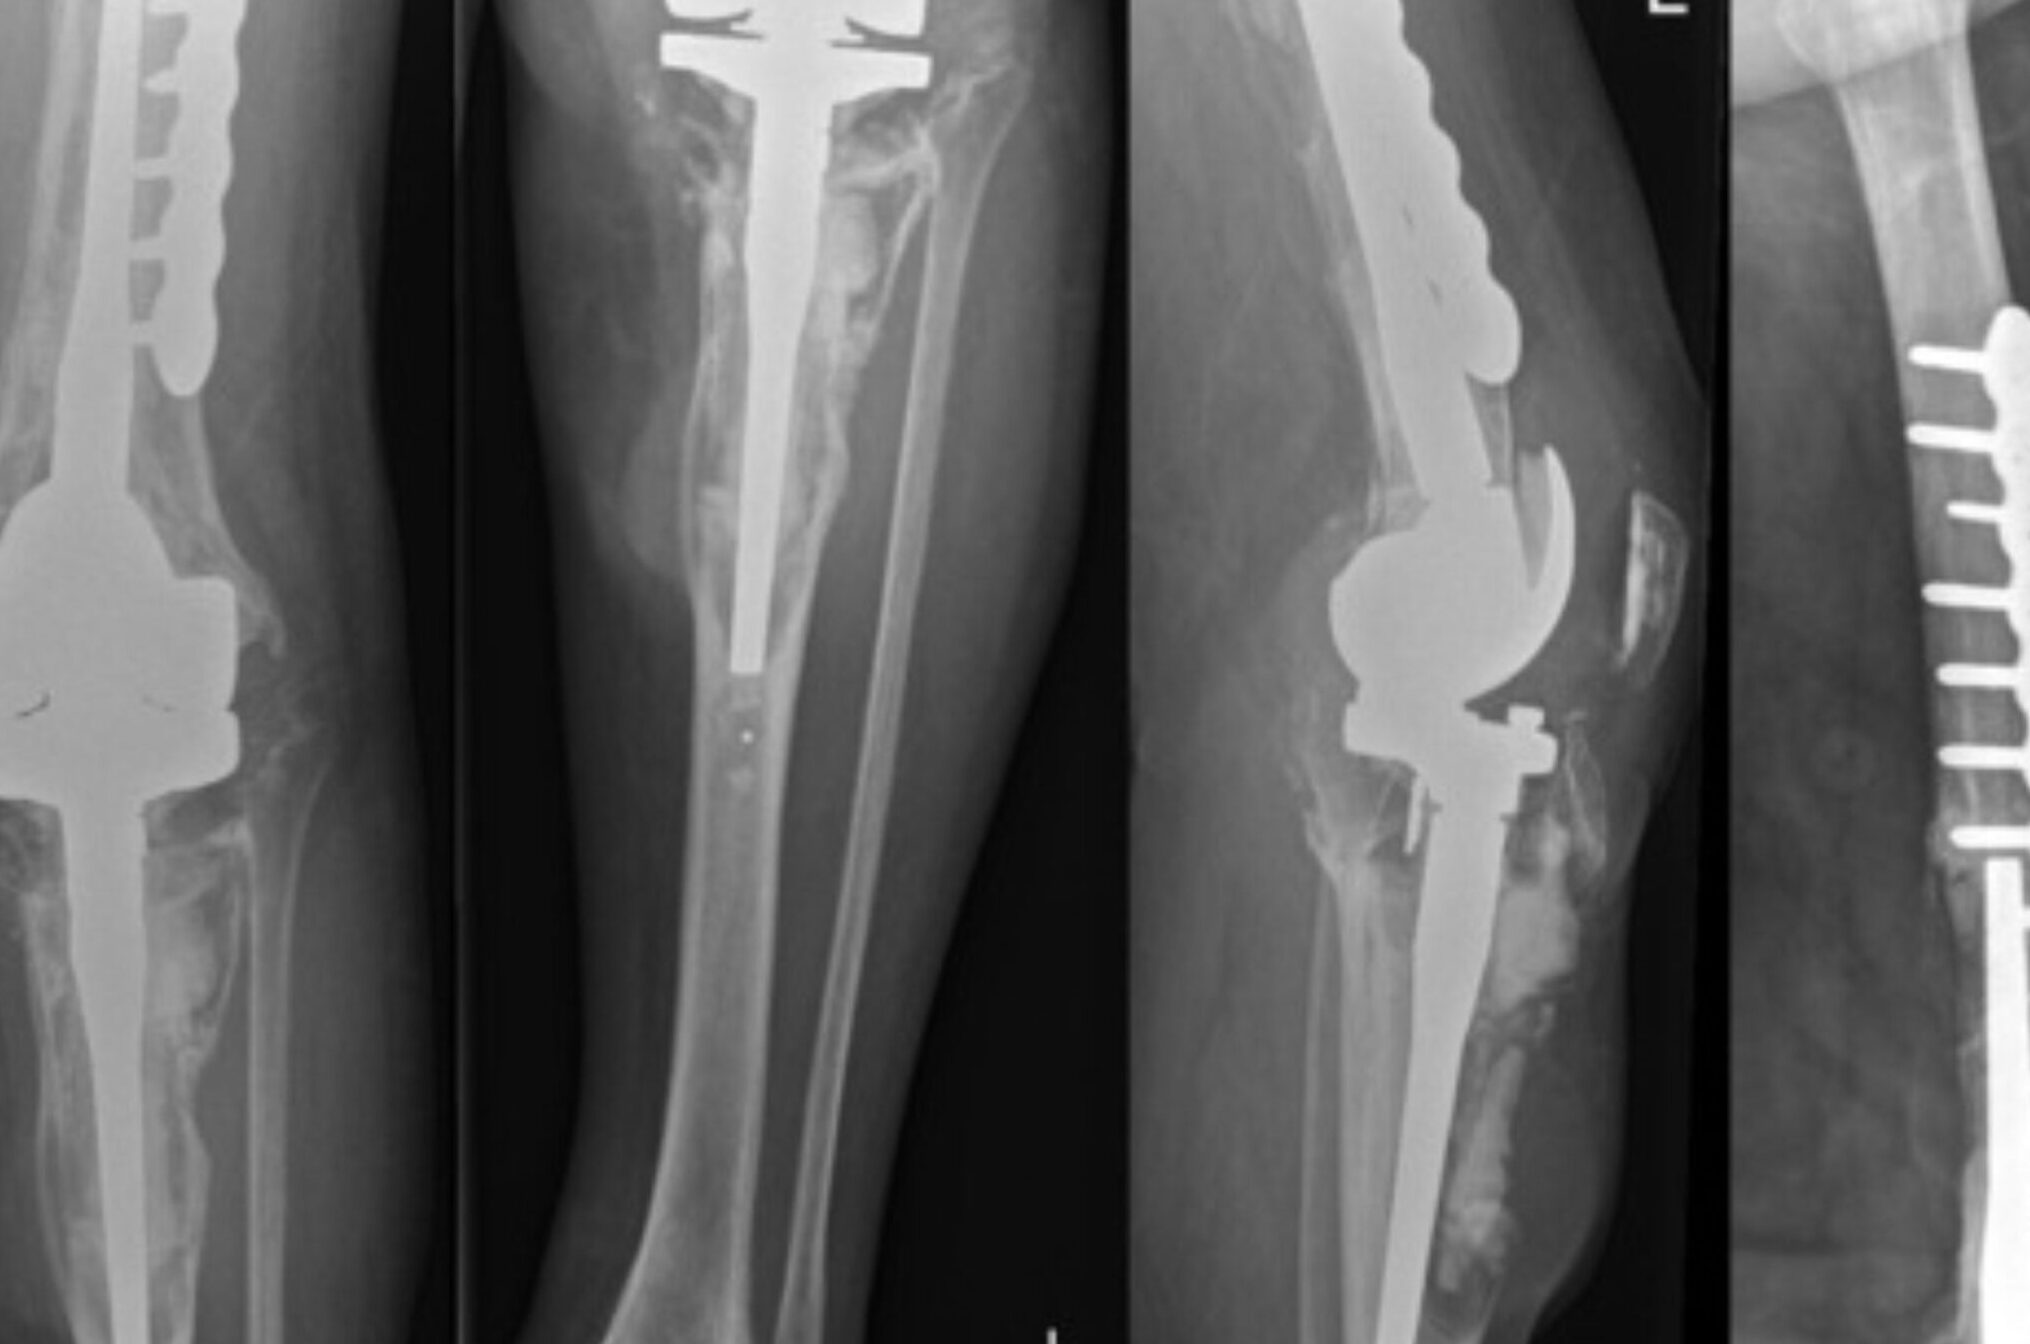

Revision for Aseptic Loosening/Infection

Aseptic loosening is the term for joint prosthetic failure that doesn't have a mechanical or infectious origin. Osteolysis (bone resorption) and an inflammatory cellular reaction within the joint are frequently linked to it.

Evaluation of Painful Knee Post Knee Replacement

A complete clinical examination and pertinent investigations are necessary for the evaluation of patients with painful total knee replacement in order to make a diagnosis. .